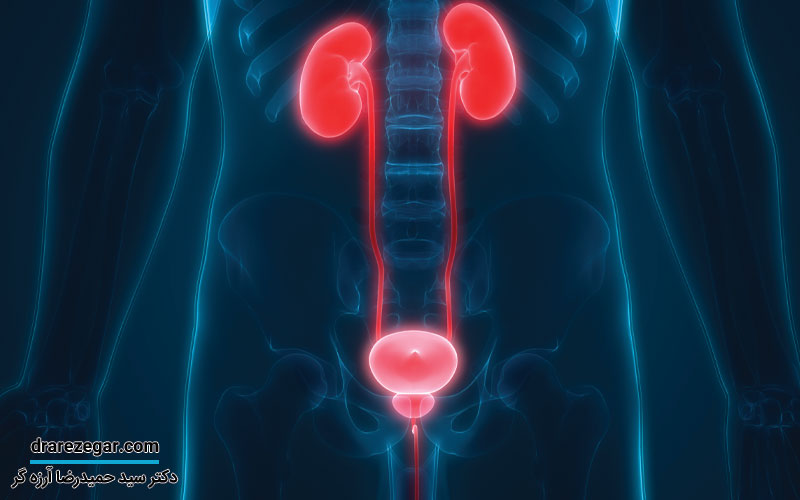

افتادگی مثانه یک مشکل شایع است که بیشتر افراد تصور می کنند فقط در زنان اتفاق می افتد، اما مردان نیز ممکن است دچار آن شوند. این مشکل معمولا به دلیل ضعف عضلات کف لگن ایجاد می شود و می تواند باعث احساس فشار در پایین شکم، تکرر ادرار، سختی در تخلیه مثانه و حتی بی اختیاری ادرار شود. عواملی مانند افزایش سن، جراحی پروستات، اضافه وزن و بلند کردن اجسام سنگین می توانند احتمال بروز این مشکل را بیشتر کنند.

افتادگی مثانه در مردان به این معنی است که عضلات و بافت های اطراف مثانه ضعیف شده و نمی توانند به خوبی از آن حمایت کنند. در نتیجه، مثانه از جای اصلی خود پایین تر می آید. این مشکل بیشتر در سنین بالا دیده می شود، اما عوامل دیگری هم ممکن است باعث آن شوند. افتادگی مثانه می تواند علائمی مثل مشکل در ادرار کردن، احساس سنگینی در پایین شکم و تخلیه نشدن کامل ادرار ایجاد کند. دلایل زیادی برای افتادگی مثانه وجود دارد. یکی از مهم ترین آن ها افزایش سن است که باعث ضعیف شدن عضلات کف لگن و مثانه می شود. همچنین، جراحی های مربوط به پروستات، بلند کردن اجسام سنگین به طور مداوم، یبوست طولانی مدت، سرفه های شدید و مکرر، اضافه وزن و برخی بیماری های عصبی که عملکرد مثانه را مختل می کنند نیز می توانند این مشکل را ایجاد کنند. در بعضی از افراد هم ممکن است عضلات لگن از ابتدا ضعیف تر باشند و باعث بروز این مشکل شوند.